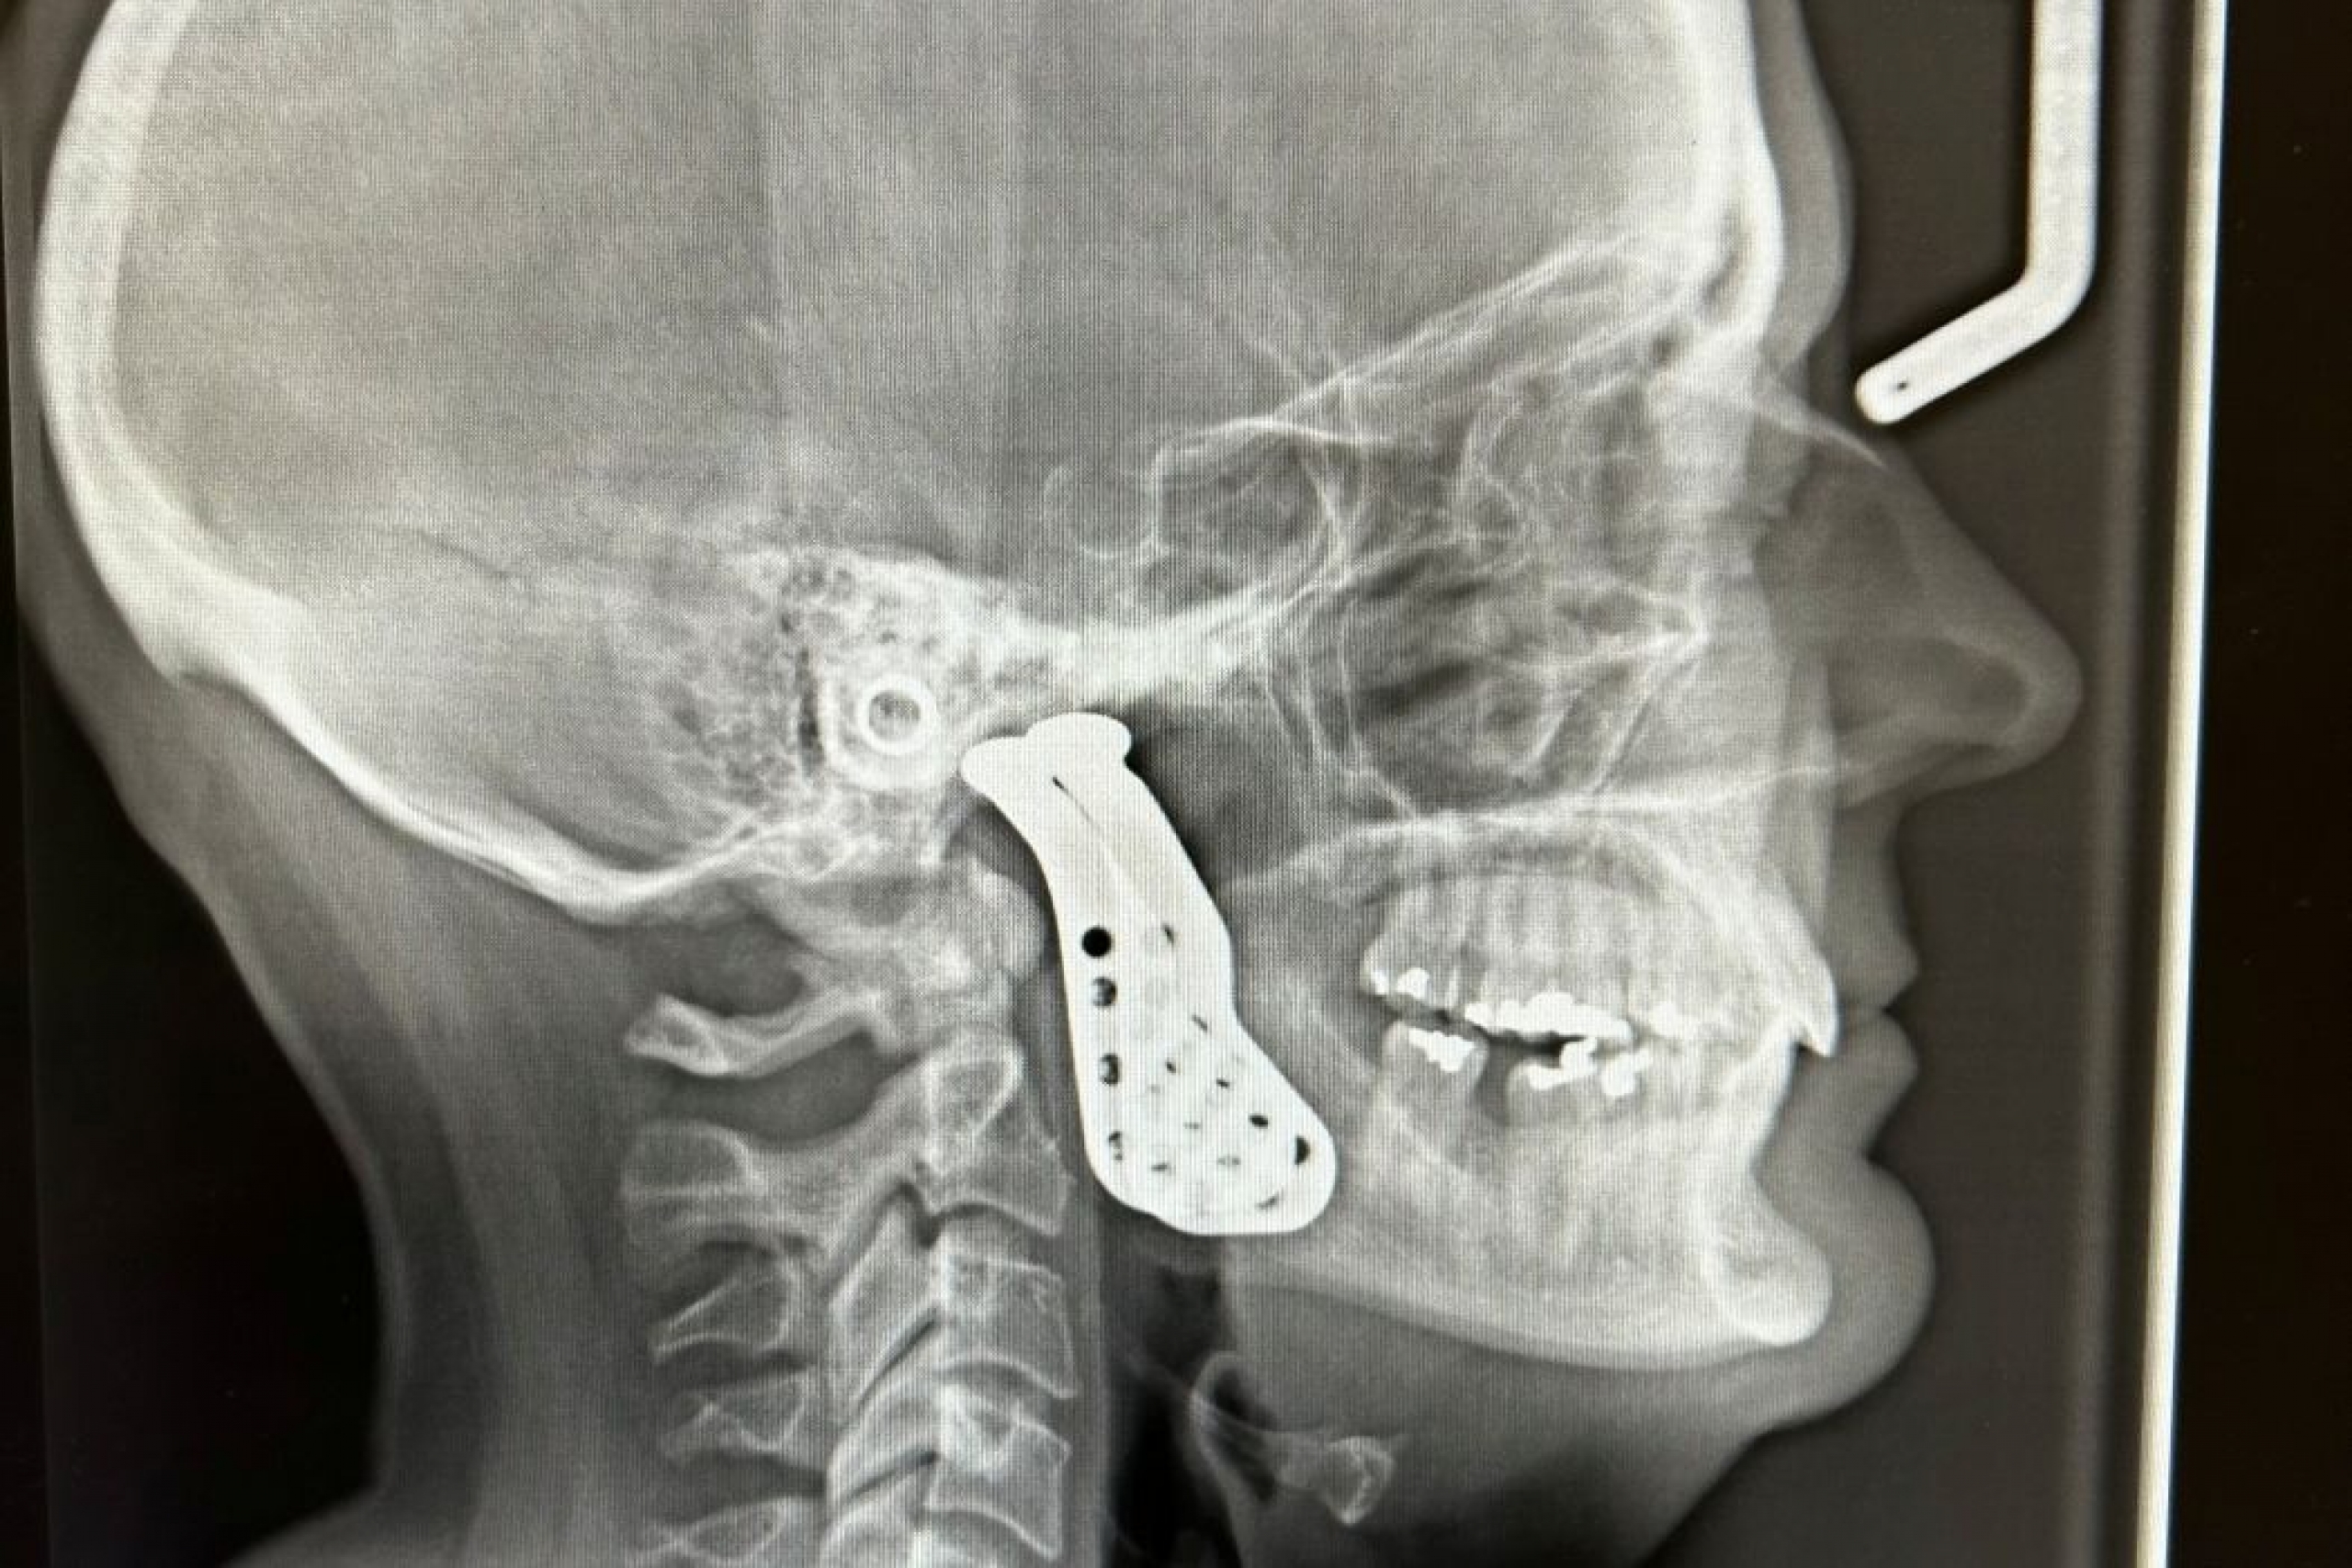

This X-ray shows the implants that were used in the jaw joint replacement surgery led by Dr. Adnan Shah.

“Once we decided there was no other treatment left but to do a total joint replacement, we took a CT scan of Kindra’s face, and based on discussions with the engineers from the manufacturing company, the specific type of implants and sizes were made,” Shah said.

“We took the diseased joint out and then placed the implants. We reconstructed part of the jawbone and the joint itself.”